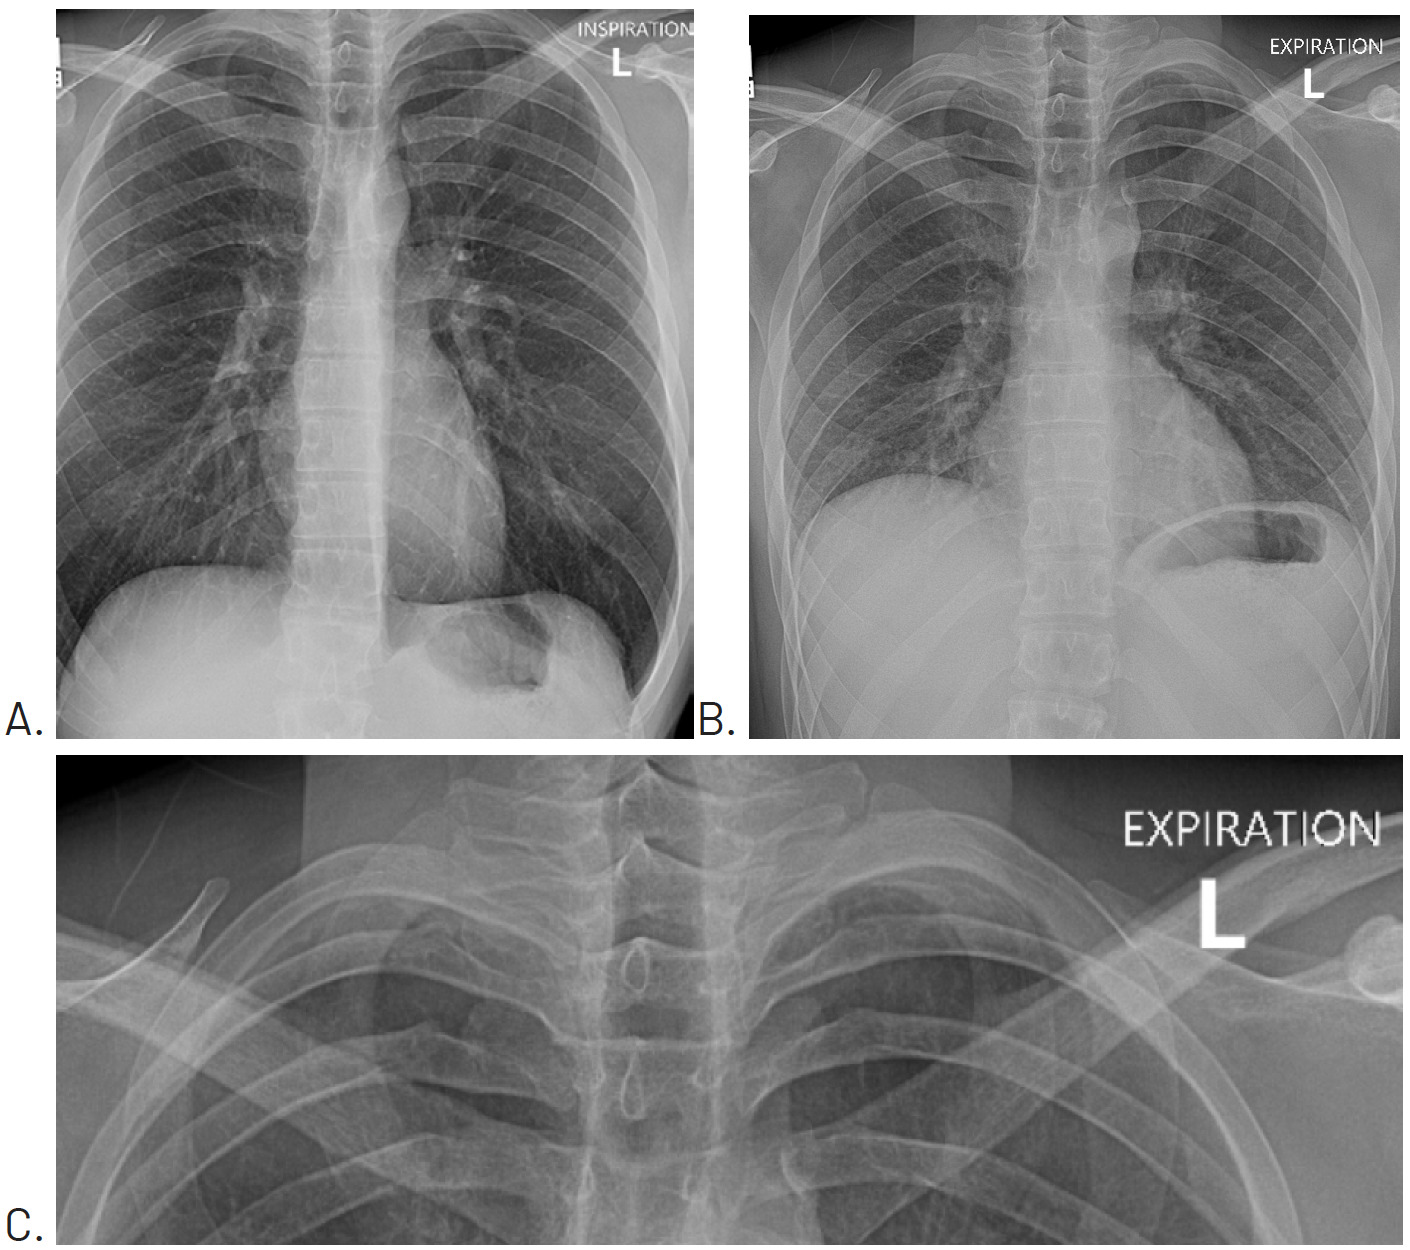

Since the patient was not currently experiencing respiratory distress, he was told to monitor his symptoms over the weekend, and that should any worsening occur in his pain or ability to breathe to seek emergency medical care. Four days later, a repeat chest x-ray with inspiration (Figure 2A) and expiration (Figure 2B) views was performed and showed that the pneumothorax had resolved.